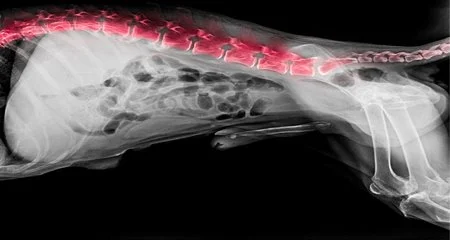

The Superiority of PennHip Over OFA

Every dog is born with a different level of connective tissue “looseness” in their hips.  Research has shown this laxity is related to the onset and prevalence of osteoarthritis throughout a dog’s life.  The looser the hip, the more problems a dog will have. Both PennHip and OFA aim to discern a dog’s hip tightness and associated CHD risk. The important difference between the two tests is the process by which they determine hip joint laxity, as well as the amount of information conveyed by the results. Simply put, PennHip takes an objective measurement that is compared to a universal database of results while all OFA offers is a subjective guestimate that is not correlated to any other findings. Let us explain.

PennHip is a time-tested, research-validated assessment involving the use of 3 separate radiographs to measure hip joint laxity.  Tests can only be performed by veterinarians who are certified in the PennHip protocol, and require the dog to be anesthetized to ensure every radiograph is taken in the appropriate, standardized way.  While immobile, the certified veterinarian takes three radiographic images of both hips.  The first image is of the hip in an extended position, meaning the legs are pulled behind the dog’s hips, similar to when they are running.   The second and third radiographs are of the hip in a neutral position, meaning the leg is directly below the hip as if the dog were standing, with two different forces applied.  In the second image, the vet introduces a compressive force similar to gravity.  In the third, the vet introduces a distraction force, pulling the leg away from the socket at a completely safe intensity.  It is worth noting that these forces to the joint are standardized so that all measures maintain consistency and significant conclusions from the data can be made.

These three images are then sent to PennHip’s lab where specialists analyze them.  They measure (once again MEASURE, not guess) the distance between the ball and socket of the joint in extension, compression and distraction.  The resulting distraction index (DI), a final number between 0 and 1, objectively demonstrates the looseness of your dog’s hips, with 0 being extremely healthy (tight hips) and 1 being extremely unhealthy (loose hips).   Because submission of results to PennHip’s database is automatic and mandatory, they have a reliable data set to compare a dog’s individual result against. This allows PennHip to quantify exactly how your dog stacks up against the entirety of the breed data, which allows us breeders to continue working towards the goal of decreasing prevalence of dysplasia by only breeding dogs that score above the average.